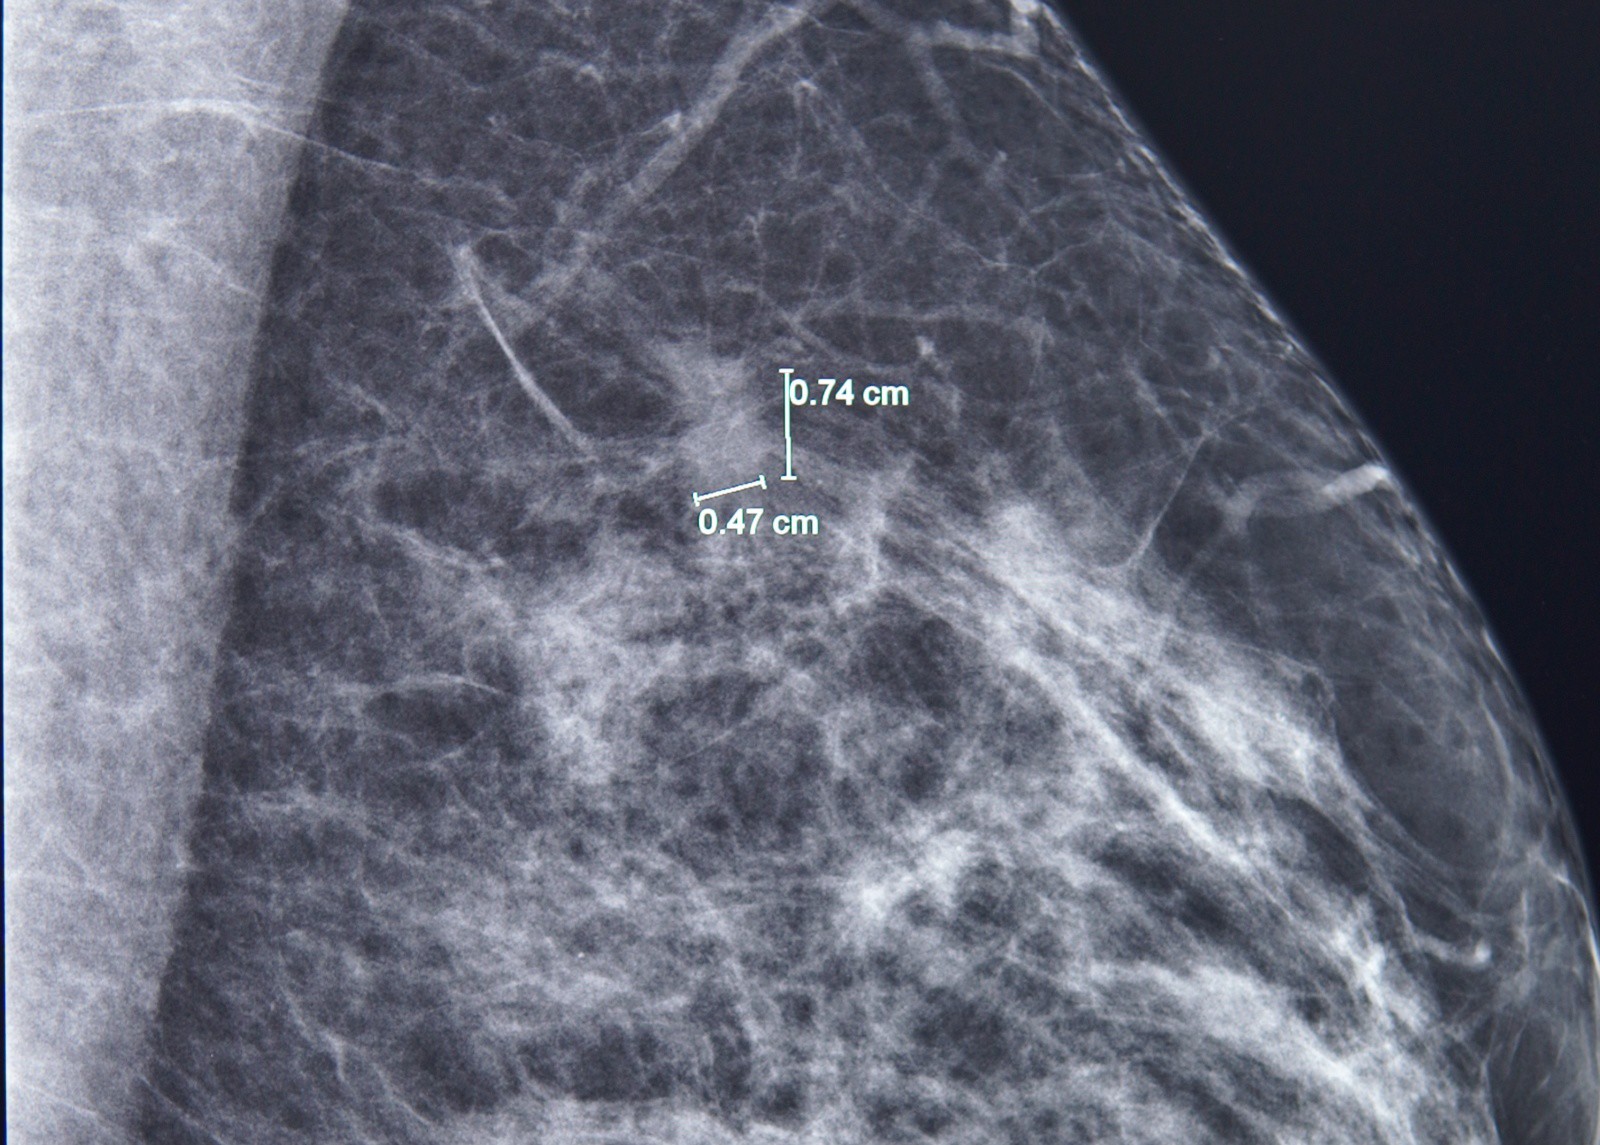

Kết quả nhũ ảnh tìm ra một tổn thương nhỏ, khoảng 7mm ở vú trái. BS.CKI Phùng Ngọc Thư - Trưởng Trung tâm Chăm sóc Tuyến vú FV cho bệnh nhân chụp thêm cộng hưởng từ (MRI) do mô vú của bà A. khá đặc. Qua phim chụp MRI, bác sĩ Thư đã phát hiện thêm một nốt tổn thương khác, chỉ 3mm.

“Khối u 3mm này quá nhỏ nên trên nhũ ảnh không thể bộc lộ, ngay cả trên MRI cũng chưa thể hiện rõ đặc điểm ác tính, dễ bị bỏ sót hoặc cho qua”, bác sĩ Thư giải thích.

Phát hiện một tổn thương 7mm ở vú trái bằng chụp nhũ ảnh. Ảnh: FV